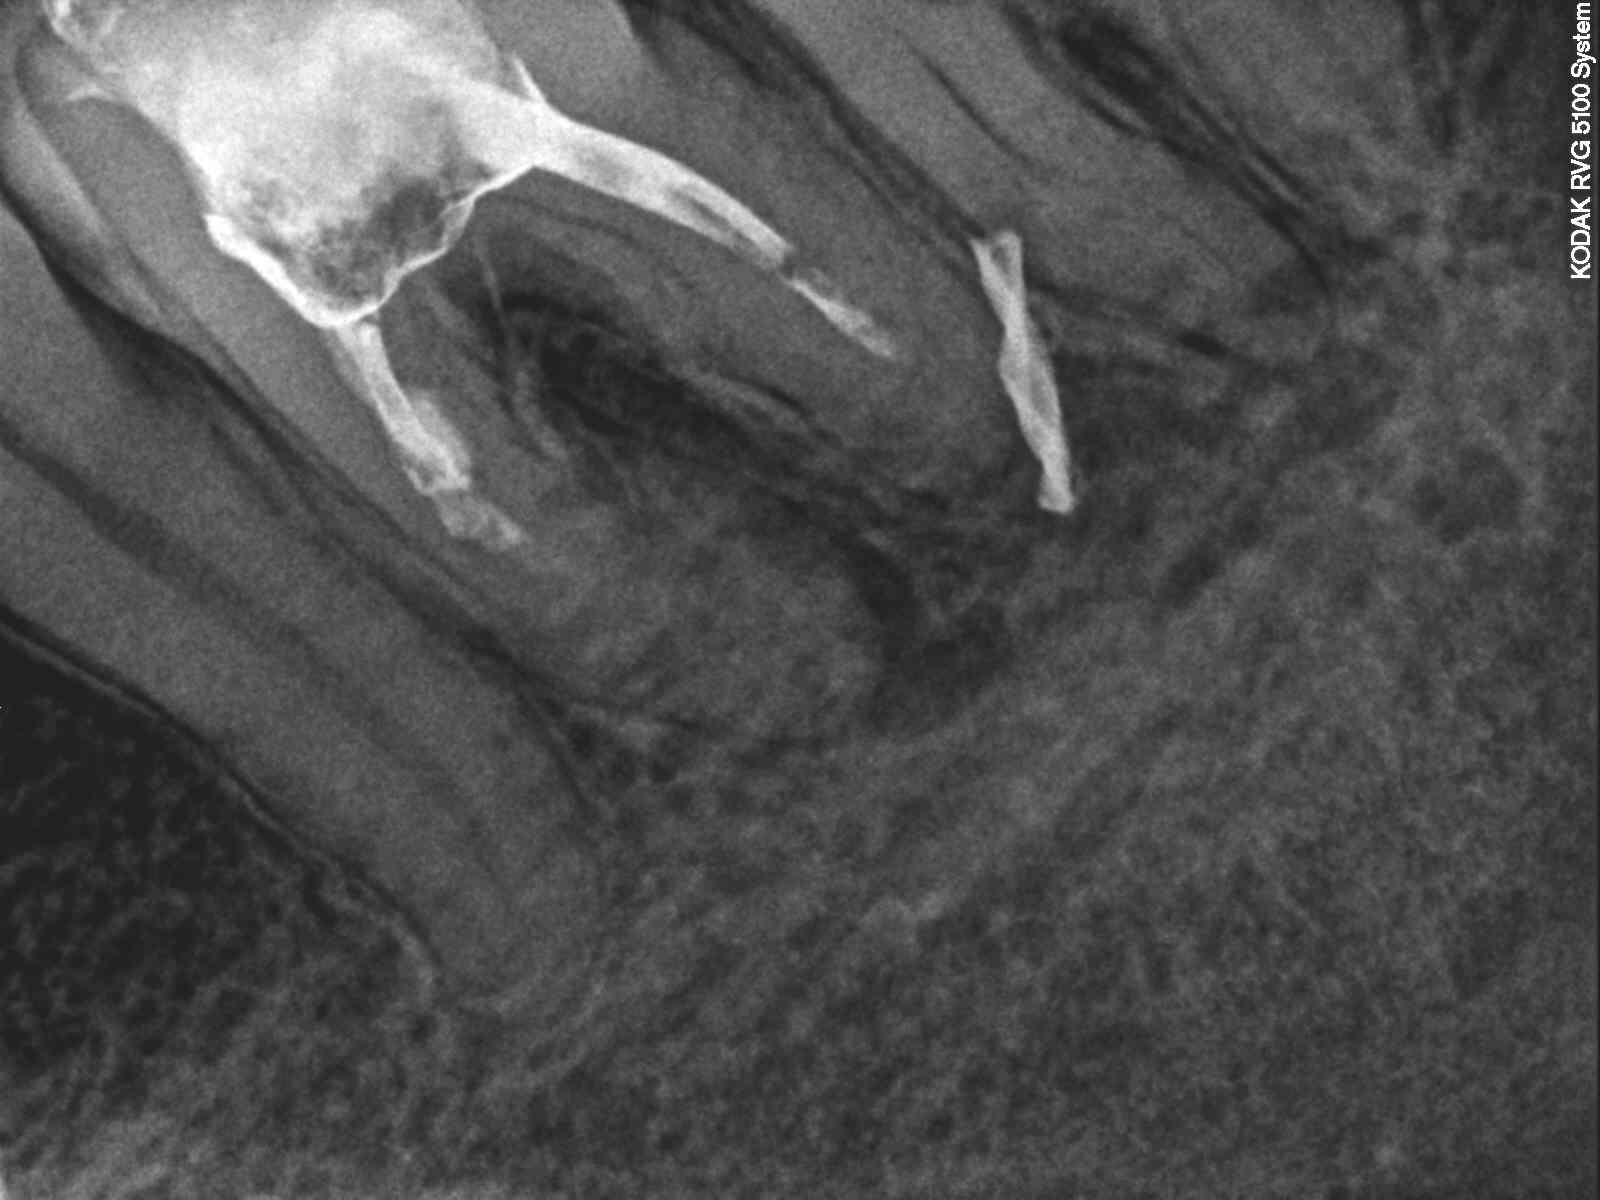

Ryc. 1. Zdjęcie rentgenowskie wykonane w chwili zgłoszenia się pacjenta do gabinetu. Kanały korzeniowe zęba 36 wypełnione częściowo dość dobrze kontrastującym się materiałem; przy wierzchołku korzenia bliższego zmiana zapalna. Pomiędzy wierzchołkiem korzenia dalszego zęba 36 a wierzchołkiem korzenia bliższego zęba 37 widoczny fragment złamanego wiertła.

2. Ząb 37 z martwą miazgą i przetoką na granicy części koronowej i środkowej korzenia bliższego. Zdjęcia rentgenowskie wykonane w gabinecie wykazały perforację korzenia bliższego zlokalizowaną około 3 mm poniżej szyjki zęba, powstałą w wyniki nawiercania kości w celu osadzenia mikroimplantu (druga próba nawiercania) oraz fragment wiertła tkwiący pomiędzy wierzchołkami korzenia dalszego zęba 36 oraz korzenia bliższego zęba 37 (trzecia próba nawiercania) (ryc. 1‑3) (film 1 i2).